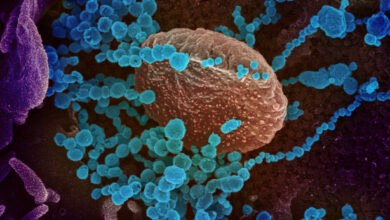

خبيرة نقص المناعة يؤدي للعديد من الأمراض

أفادت اختصاصية التغذية الروسية، ريما مويسينكو، نقص المناعة في الجسم يعرض الجسم للمرض والتعب ونزلات البرد خلال الخريف. وقالت…